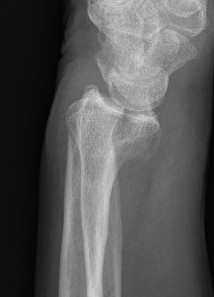

Distal Radius Angles

- radial volar tilt 11°

- radial inclination  22°

- radius is 11 mm longer than ulna

- ulna variance 2mm positive on average

Distal Radius NormalNormal Radial InclinationNormal Radial Length